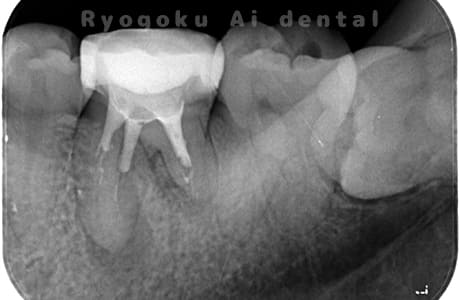

Case01

-

根管内の異物

- 原因

- 根管内異物(ファイル破折)による慢性根尖性歯周炎

- 治療期間

- 3ヶ月

- 治療内容

- マイクロスコープを使用した根管内異物除去並びにマイクロエンド

- 治療費用

- 121,000円(ファイル除去費用も込み)

他院で細い器具(ファイル)が根管内に破折した状態で、咬合痛を主訴に来院された患者様です。ファイルをマイクロスコープ下で除去し、根管治療を行ないました。